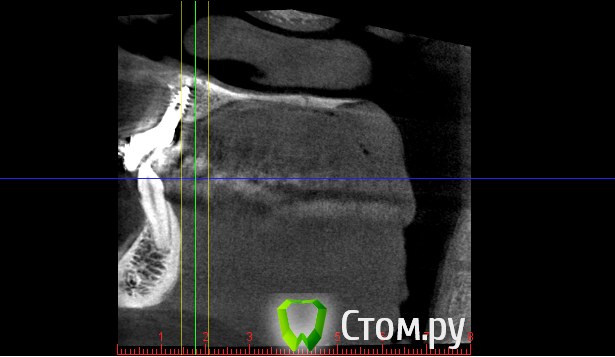

***Irene*** Опубликовано 22 октября, 2014 Поделиться Опубликовано 22 октября, 2014 (изменено) Уважаемые знатоки!Сделали КТ верхней челюсти с имплантом, потому что коронку ну никак не вместить по человечески, десна ходуном ходит, и увидели такую картину (см картинки). То, что имплант стоит слишком глубоко в нёбо и не в зубном ряду - видно даже невооруженным и непрофессиональным взглядом, шейка коронки, как видно на снимке, под большим углом, но коронка все равно торчит вперед.В общем, вердикт доктора - удалять и ставить новый с предварительной аугментацией. Сразу скажу, что в клинике, в которой ставили, клялись, что это нормально, но я оттуда сбежала, вердикт уже из новой клиники.Вопросы:1) На самом ли деле имплант стоит в кости криво?2) Не опасно ли удаление прижившегося импланта и какие могут быть последствия?3) Какова последовательность в данном случае: удаление+аугментация, затем новая имплантация через полгода, затем коронка через полгода? Изменено 22 октября, 2014 пользователем ***Irene*** Ссылка на комментарий

anvladd Опубликовано 23 октября, 2014 Поделиться Опубликовано 23 октября, 2014 (изменено) на 3 кт видно что он косо стоит. Изменено 23 октября, 2014 пользователем anvladd Ссылка на комментарий

***Irene*** Опубликовано 23 октября, 2014 Автор Поделиться Опубликовано 23 октября, 2014 Ну, в общем-то, внутри рта это выглядит именно так, как на 3 КТ - смещение из зубного ряда, причем, нормальное такое. Врач говорит, что это из-за того, что на КТ 4 недостаток кости с внешней стороны и что процесс будет усугубляться, поэтому нужно нарастить кость, удалив этот имплант, и вставить новый. Фиг с ней, с кривизной, больше волнует вопрос, на самом ли деле там спереди не хватает кости и она может "уйти" окончательно, из-за чего имплант вывалится сам? И не развезет ли мне всю челюсть удалением импланта (ведь он же врос в кость), что потом всякие косметические операции понадобятся и пр. Ссылка на комментарий